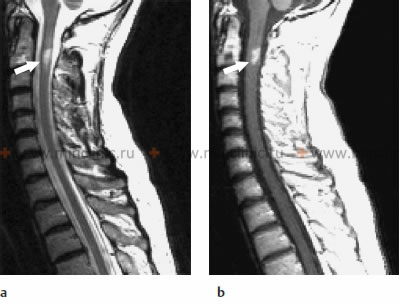

МРТ шейного отдела спинного мозга при инфекцонном миелите: а - на сагиттальной T2-взвешенном изображении показано поражение с гиперинтенсивным сигналом в спинном мозге на уровне С2 тела позвонка; b - на Т1-взвешенном изображении после введения контрастного вещества отмечены усиление рисунка.

МРТ шейного отдела спинного мозга при инфекцонном миелите: c - на аксиальном T2-взвешенном изображение видно, что поражение спинногом мозга занимает его центральную часть; d - усиление рисунка участка поражения спинного мозга на аксиальном T1-взвешенном изображении после введения контрастного вещества.